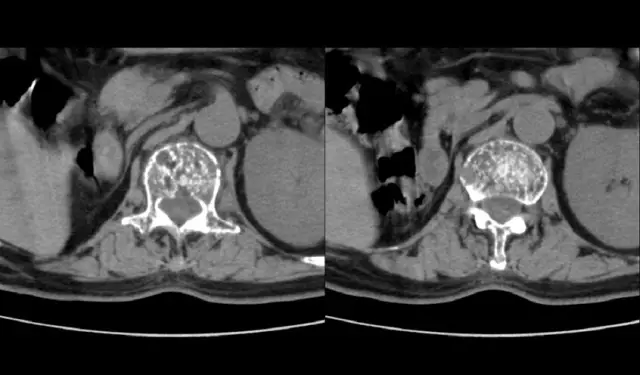

58岁的唐女士在4个月前由于干体力活下蹲站起来后突然出现胸背、下腰部酸胀疼痛,伴随着活动的限制,她长时间的行走、站立以及弯腰导致劳累使至病情加重了,休息后并可以缓解疼痛。唐女士得知这个病情后,并到当地医院求治,诊断为“腰椎间盘突出症”,经过当地医院的治疗,效果不佳。在半个月前,唐女士由于侧身起床后病情更加严重了,为了更一步的进行治疗,今日并来我院求治。

我院门诊专家就唐女士的病情被初步诊断为“胸腰椎退行性骨关节病”收入住院治疗。入院后,经专家们对唐女士进一步的检查被确诊为患有多发性骨髓瘤、腰椎椎体压缩骨折、高钙血症、腰椎间盘突出症、骶管囊肿,同时还患有严重骨质疏松症。